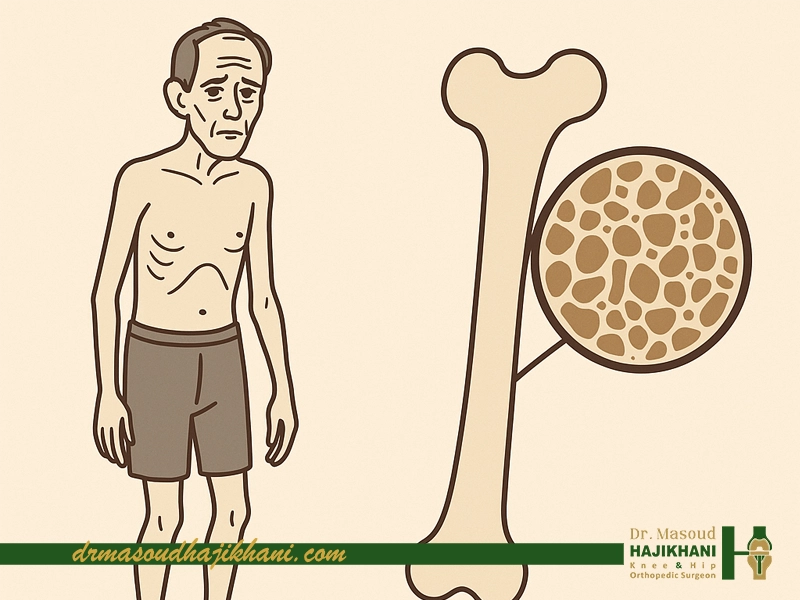

پوکی استخوان بهطور مستقیم باعث لاغری نمیشود. این بیماری فقط بر تراکم استخوان اثر میگذارد و ماهیت آن کاهش وزن یا کم شدن چربی بدن نیست. اما برخی شرایط همراه پوکی استخوان میتوانند باعث کاهش وزن شوند یا شکل بدن را طوری تغییر دهند که فرد «احساس لاغری» کند، حتی اگر وزن او روی ترازو کم نشده باشد.

یکی از علتهای مهم، تحلیل رفتن عضلات است. وقتی فرد به دلیل درد استخوان یا ترس از شکستگی کمتر حرکت میکند، عضلهها بهمرور تحلیل میروند. این تغییر بیشتر در ظاهر بدن مشخص میشود. فرد ممکن است وزن زیادی کم نکرده باشد اما احساس کند «آب شده است».

همچنین شکستگیهای ریز مهرهها در پوکی استخوان میتوانند باعث قوز کمر یا جمع شدن بدن شوند و فرد خود را لاغرتر ببیند. این احساس بیشتر ناشی از تغییر فرم بدن است، نه کاهش واقعی وزن.